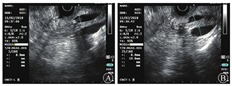

2019年1月30日行内镜下鼻胆外引流管变更内引流支架术(图2)。术后患者食欲改善,2周内体质量增加5 kg。2月11日患者出现发热,体温为37.7 ℃,上腹部疼痛,伴后背放射痛。查血常规未见异常,血生物化学检查示AST水平为88.2 U/L,胆红素水平在正常范围内,血淀粉酶水平为174.1 U/L(正常参考值为0~150.0 U/L ),血脂肪酶水平为352.7 U/L(正常参考值为13.0~60.0 U/L),不排除因乳头占位压迫胰管可能,予禁食水、对症支持治疗。2月13日行十二指肠乳头肿物内镜下切除术+超长胆胰管支架转流(鼻胆外引流管改造)术。术中先行超声内镜检查,初步评估乳头部占位无明显胆管、胰管内生性生长,但胰管扩张明显(图3)。考虑乳头病变浸润相对较深,为避免肿瘤组织残留或复发,切除乳头病变时尽量深切,术后创面可见固有肌层显露。为避免胰液或胆汁刺激创面而引起迟发出血或穿孔,术中置入鼻胆外引流管改造的超长(约35 cm)胆胰管支架转流,将胰液和胆汁跨过乳头切除创面引流至远端空肠,创面予金属夹夹闭(图4)。术后病理结果(图5)提示十二指肠乳头壶腹部低分化腺癌,癌旁和表浅腺体呈管状-绒毛状腺瘤改变,癌灶大小约1.5 cm×1.0 cm×0.5 cm,癌组织侵犯十二指肠肠壁肌层,紧邻基底切缘(切缘电凝变性显著)。术后当天和第2天胃管内共引流出约220 mL血性液体,发热,体温最高38.5 ℃,右上腹疼痛,查体无腹膜刺激征。复查血红蛋白较前无明显下降,白细胞计数为9.17×109/L,中性粒细胞占比为0.81,IL-6水平为80.4 ng/L,血淀粉酶水平为183.3 U/L,血脂肪酶水平为292.26 U/L,余未见明显异常。予以禁食水、抗感染(静脉注射亚胺培南西司他丁钠,1 g/8 h)、止血(经静脉泵注射艾司奥美拉唑、生长抑素,静脉注射酚磺乙胺、卡洛磺钠,口服凝血酶冻干粉等)、静脉营养支持等治疗。患者胃管内出血逐渐停止,腹痛渐缓解,1周后拔除胃管,逐步恢复饮食。患者于2019年5月31日至解放军总医院第一医学中心复查,十二指肠检查结果未见异常,活组织病理学检查示慢性炎,正电子发射计算机断层显像(PET-CT)检查未见明确肿瘤残留、复发或远处移位。2019年10月外院复查腹部增强CT亦未见明显异常。遂继续随访观察至今,患者无明显不适。

消化内科李明阳副主任医师:近年来,内镜下切除术已逐步成为十二指肠乳头肿瘤的一线治疗方法,然而手术适应证尚未明确。目前较为统一的适应证如下:肿瘤组织仅限于壶腹部,无内镜下恶性肿瘤证据(溃疡性、易碎性和自发性出血),无导管(胆管、胰管)内生性生长,十二指肠固有肌层无侵犯,瘤体组织最大径<4 cm或<5 cm等[5,6]。术前乳头病变的准确评估至关重要,需从多方面进行。术前镜下乳头活组织检查的准确率为62%~85%,有相对较高的假阴性率,可能无法完整反映病变性质[7,8]。内镜超声在评估十二指肠乳头肿瘤导管内生性生长方面的准确性与ERCP相当,而且能够准确判断肿瘤局部T分期[9],但其对淋巴结转移的诊断困难。然而,即使完善上述检查,术前早期准确诊断也非常困难。该患者在解放军总医院第一医学中心内镜下切除术前曾先后2次行乳头活组织检查均未提示高级别瘤变或癌变,内镜下切除术前亦通过腹部CT、MRCP、超声内镜等检查除外导管内生浸润,充分评估后选择内镜下切除治疗,但术后病理提示低分化腺癌,癌组织侵犯十二指肠肠壁肌层。严格意义上来说,该患者并不适合内镜下切除,需追加外科手术以避免术后残留或复发。